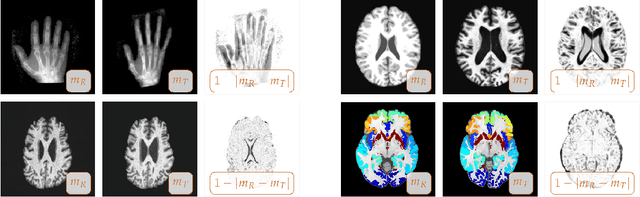

Abstract:We study the performance of CLAIRE -- a diffeomorphic multi-node, multi-GPU image-registration algorithm, and software -- in large-scale biomedical imaging applications with billions of voxels. At such resolutions, most existing software packages for diffeomorphic image registration are prohibitively expensive. As a result, practitioners first significantly downsample the original images and then register them using existing tools. Our main contribution is an extensive analysis of the impact of downsampling on registration performance. We study this impact by comparing full-resolution registrations obtained with CLAIRE to lower-resolution registrations for synthetic and real-world imaging datasets. Our results suggest that registration at full resolution can yield a superior registration quality -- but not always. For example, downsampling a synthetic image from $1024^3$ to $256^3$ decreases the Dice coefficient from 92% to 79%. However, the differences are less pronounced for noisy or low-contrast high-resolution images. CLAIRE allows us not only to register images of clinically relevant size in a few seconds but also to register images at unprecedented resolution in a reasonable time. The highest resolution considered is CLARITY images of size $2816\times3016\times1162$. To the best of our knowledge, this is the first study on image registration quality at such resolutions.